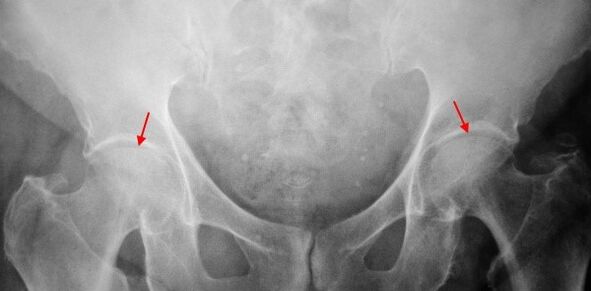

On the X -Ray of the patient with Coxarthrosis at level 1, the slight changes are determined: The uneven narrowing of the joint distance, as well as the development of the bones around the outer or inside of acetabulum when there is no change from the head and neck of the femur.

In the image of x -ray for the Coxarthrosis of level 2, the uneven narrowing of the joint distance (more than half of the normal height) is determined.The thigh tip has changed, deformed and increased in size, and its borders become uneven.Bone growth with this COXARTHROSIS level is not only inside but also at the outer edge of acetabulum and goes out of cartilage.

On the X -ray for Coxarthrosis of level 3, the narrowing of the joint distance, a significant expansion of the thigh tip and the development of many bones were detected.

Diagnosis of Coxarthrosis is based on clinical signs and data of additional studies, which is X -ray.In many cases, X -Rays can set up not only the degree of Coxarthrosis, but also the cause.Therefore, for example, the increase of the diahyseal corner, scenes and flatten acetabulum shows that dysplasia, and changes in the shape of the feminine part of the femur are indicated that Coksartrosis is the consequence of pertes or youthful molecules.On the X -ray of patients with Coxarthrosis, changes may also be detected to show injuries.